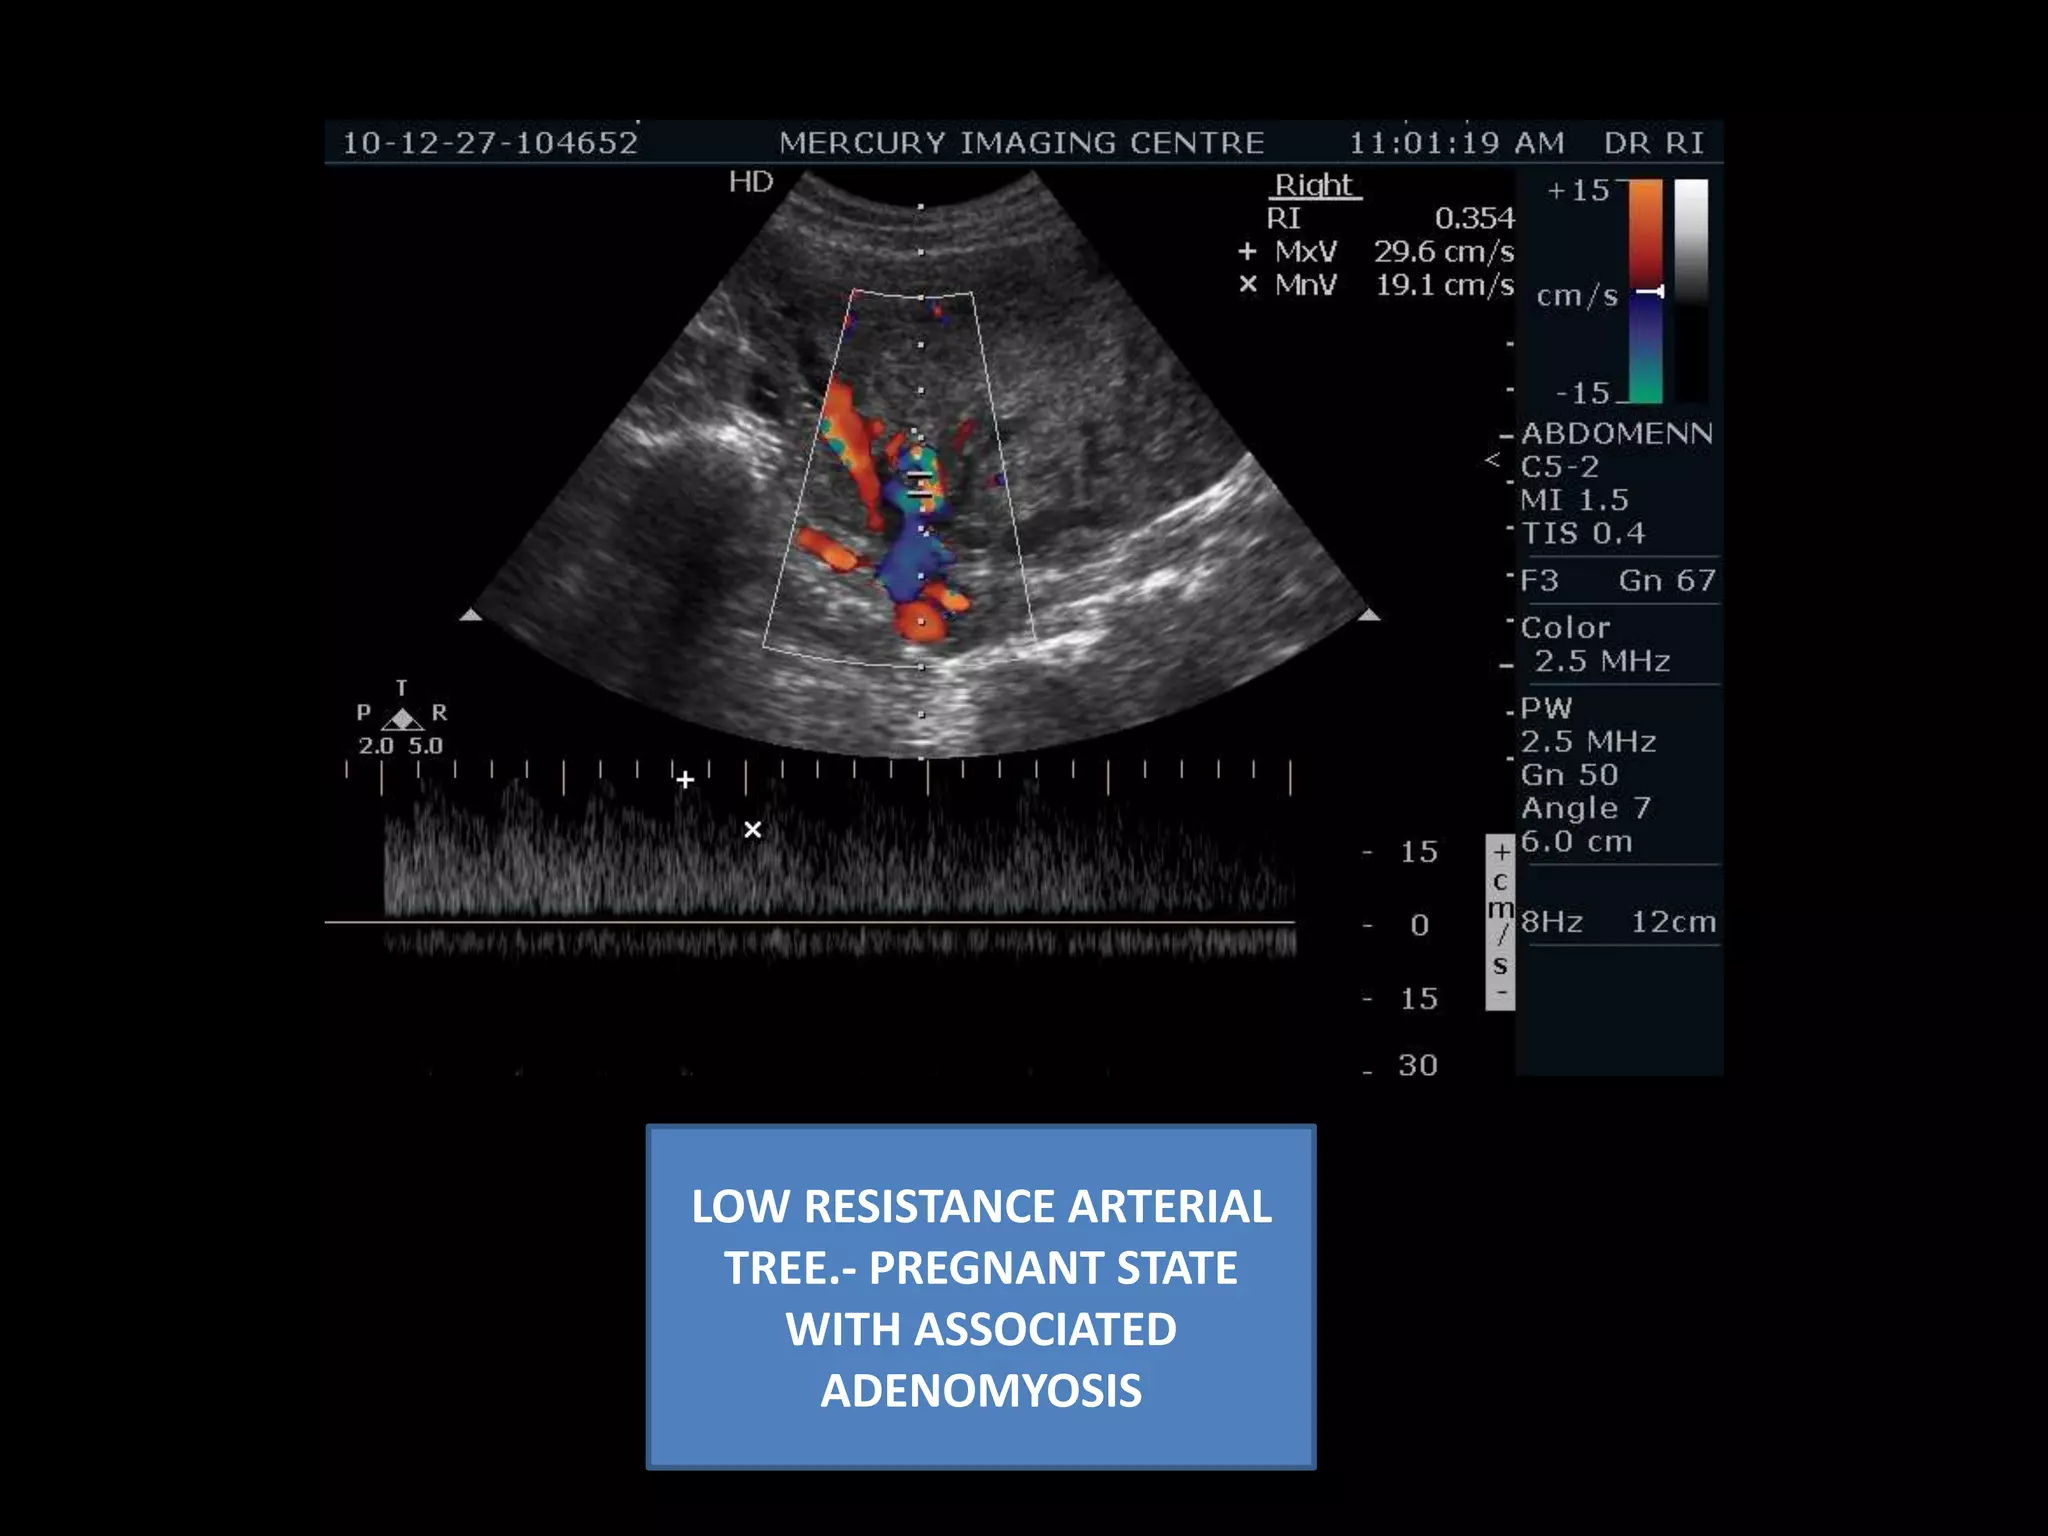

LOW RESISTANCE ARTERIALTREE.- PREGNANT STATE WITH ASSOCIATED ADENOMYOSIS

VALSALVAE ---- Tortuosvenous channels- normal response. – Pregnanacy with adenomyosis – Associated component of pelvic congestion.